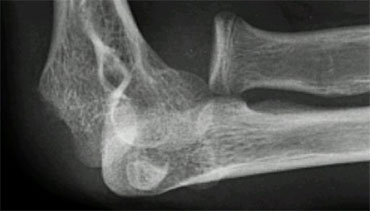

Gartland type III fracture Gartland type III fracture

Gartland type III fractures are completely dislocated and are at risk for malunion and neurovascular complications (figure).

They require reduction by closed or if necessary open means. Stabilisation is maintained with either two lateral pins or medial lateral cross pin technique.